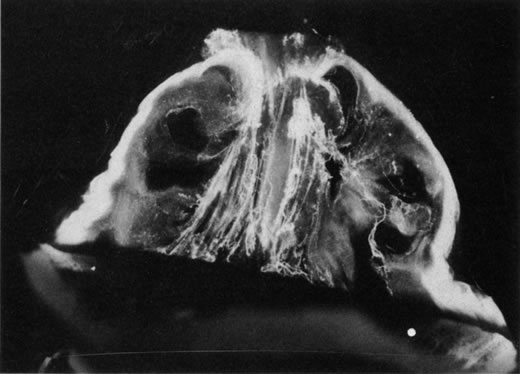

The retina is usually not involved in anterior PHPV. Indeed, previous studies have suggested that the anterior form is due to a primary defect in lens development and that vitreous changes are all secondary.34 This postulate has never been substantiated. There are rare instances of posterior PHPV in which opaque connective tissue arises from Bergmeister's papilla and persistent hyaloid vessels (Fig. 1).32,35 These can cause congenital falciform folds of the retina and, if severe, can cause tentlike retinal folds, leading on rare occasions to tractional and/or rhegmatogenous retinal detachment. Font and investigators36 demonstrated the presence of adipose tissue, smooth muscle, and cartilage within the retrolental plaque and suggested that PHPV arises from metaplasia of mesenchymal elements in the primary vitreous.

Fig. 1. Persistent hyperplastic primary vitreous (PHPV). A wide-angle fundus photograph of the left eye in a 10-year-old boy with the posterior form of PHPV demonstrates a fibrous stalk arising from the optic disc and extending into the central vitreous. (Sebag J: The Vitreous: Structure, Function and Pathobiology, p 99. New York, Springer-Verlag, 1989.)